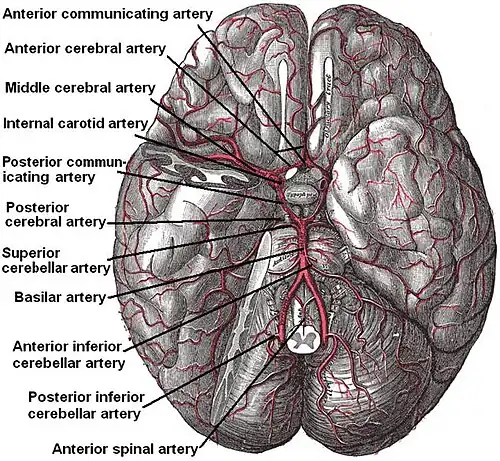

Diagram of the arterial circulation at the base of the brain (inferior view), the circle of Willis is drawn in the upper half. Blood flows up to the brain through the vertebral arteries and through the internal carotid arteries. | |

The circle of Willis (also called Willis' circle, loop of Willis, cerebral arterial circle, and Willis polygon) is a circulatory anastomosis that supplies blood to the brain and surrounding structures in reptiles, birds and mammals, including humans.[1] It is named after Thomas Willis (1621–1675), an English physician.[2]

The circle of Willis is a part of the cerebral circulation and is composed of the following arteries:[3]

- Anterior cerebral artery (left and right) at their A1 segments

- Anterior communicating artery

- Internal carotid artery (left and right) at its distal tip (carotid terminus)

- Posterior cerebral artery (left and right) at their P1 segments

- Posterior communicating artery (left and right)

The middle cerebral arteries, supplying the brain, are also considered part of the Circle of Willis [4]

The left and right internal carotid arteries arise from the left and right common carotid arteries.

The posterior communicating artery is given off as a branch of the internal carotid artery just before it divides into its terminal branches - the anterior and middle cerebral arteries. The anterior cerebral artery forms the anterolateral portion of the circle of Willis, while the middle cerebral artery does not contribute to the circle.

The right and left posterior cerebral arteries arise from the basilar artery, which is formed by the left and right vertebral arteries. The vertebral arteries arise from the subclavian arteries.

The anterior communicating artery connects the two anterior cerebral arteries and could be said to arise from either the left or right side.

All arteries involved give off cortical and central branches. The central branches supply the interior of the circle of Willis, more specifically, the Interpeduncular fossa. The cortical branches are named for the area they supply and do not directly affect the circle of Willis.